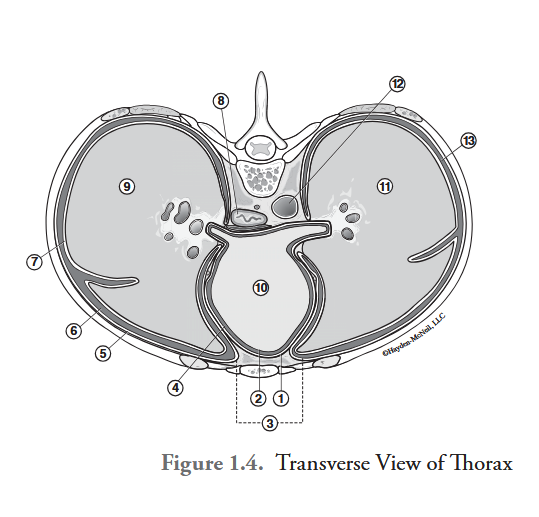

What is labeled #1?

parietal pericardium

What is labeled #2?

visceral pericardium (epicardium)

What is labeled #3?

mediastinum

What is labeled #4?

pericardial cavity

What is labeled #5?

parietal pleura

What is labeled #6?

right pleural cavity

What is labeled #7?

visceral pleura

What is labeled #8?

esophagus

What is labeled #9?

right lung

What is labeled #10?

heart

What is labeled #11?

left lung

What is labeled #12?

descending aorta

What is labeled #13?

left pleural cavity